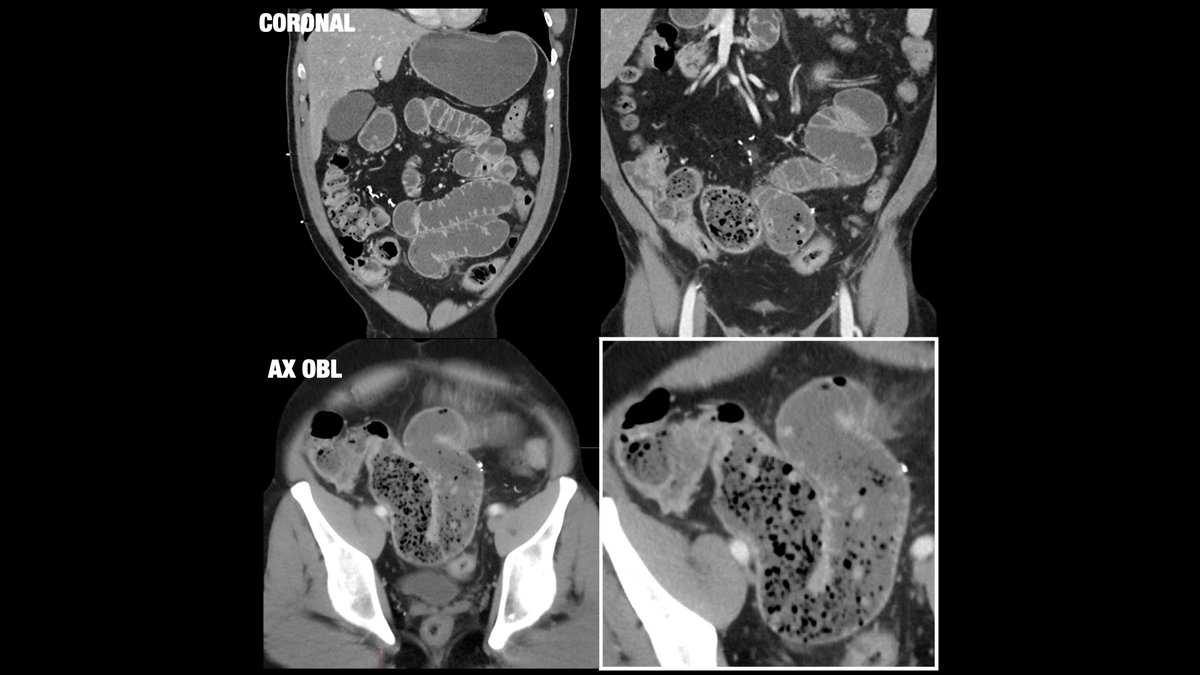

61-year-old male with history of prior appendectomy presenting with nausea/vomiting. Diagnosis? What is the name of this sign? Brigham and Women's Radiology FOAMrad SAR Resident and Fellow Section Future Radiology Residents CBR #MedEd